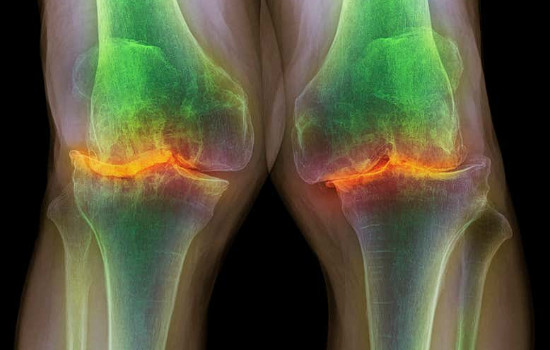

Radiografia dos joelhos de um homem de 87 anos com osteoartrite grave. (Foto: Reprodução)

Testes em pequenos roedores e em células humanas trouxeram resultados promissores para quem sofre com doenças como artrite e condromalácia patelar — um desgaste da articulação do joelho que leva ao aparecimento de dores intensas. O estudo realizado na Universidade de Oklahoma (EUA) apresentou uma nova abordagem no tratamento do desgaste: foi desenvolvido um lubrificante artificial inspirado no líquido sinovial – o líquido dentro das articulações.

Com isso, joelhos com artrite dolorosa poderão ser tratados com injeções do fluido lubrificante, que imita a versão natural encontrada nas articulações. Esse fluido permite que as articulações danificadas se reparem. Os ratos do experimento aumentaram a regeneração da cartilagem com osteoartrite — resultado do desgaste relativo ao envelhecimento — após a aplicação do tratamento.